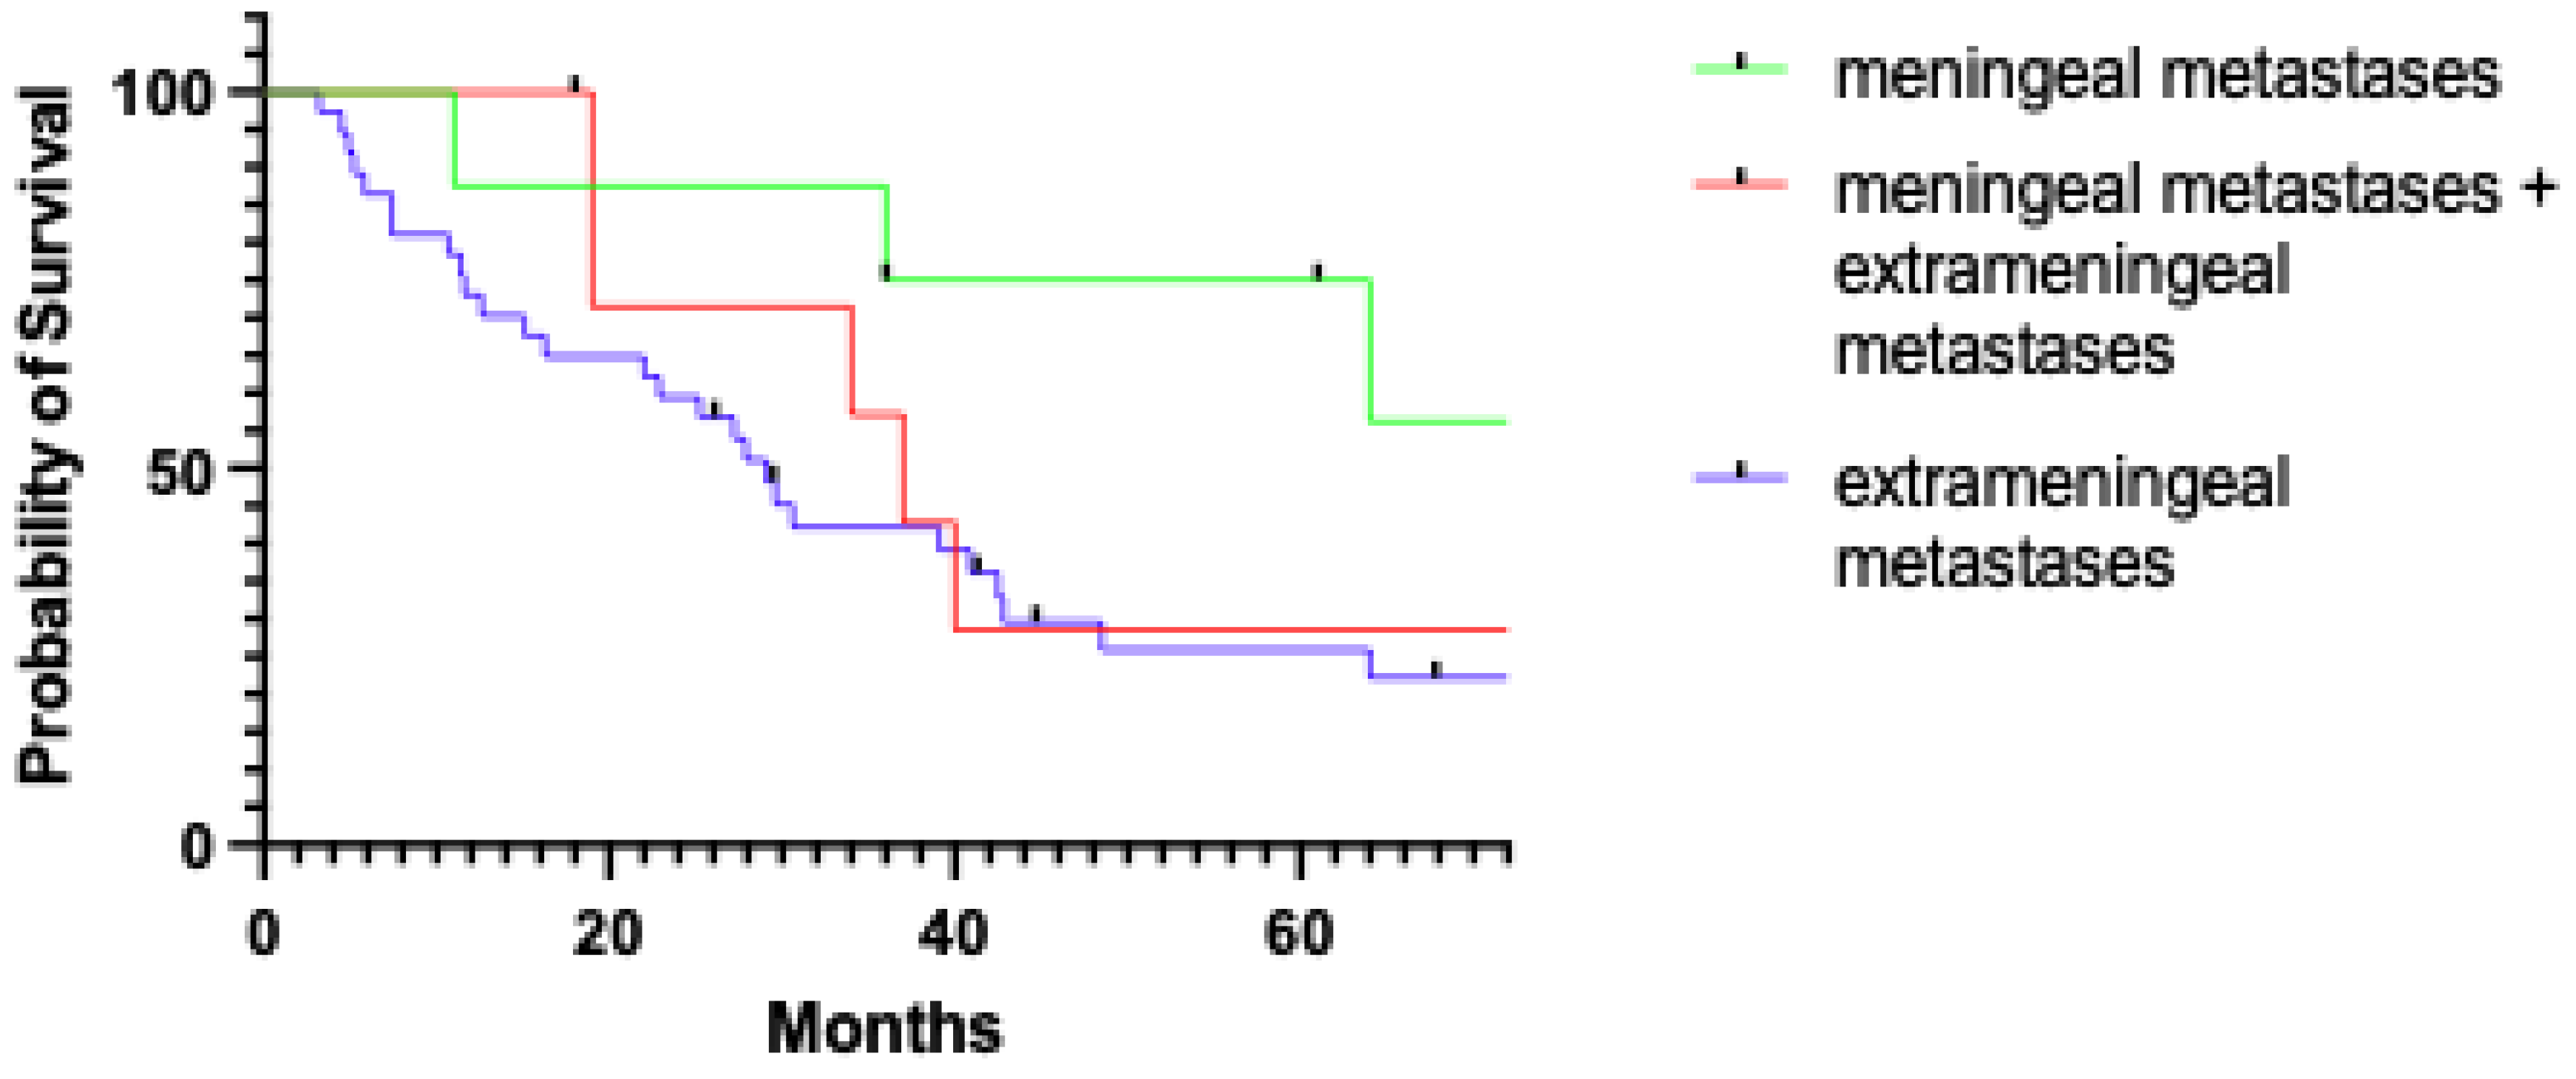

Figure 2 shows the overall survival in patients with MM who underwent active treatment versus best supportive care.

The median follow-up was 37 months (range: 11–206 months). At the latest follow-up evaluation, 8 patients (47.1%) were dead of disease, 1 patient was dead of other causes (5.9%), and 8 patients were alive with disease (47.1%). The latency between diagnosis and meningeal recurrence was 31.6 months (range: 1.6–122.9 months). The median survival after the treatment performed at our institution was 35 months (range: 6–178 months). The median survival after the diagnosis of MM was 21 months (range: 10–27 months) in the entire group and 11 months (range: 0–111 months) in the group of patients dead of disease.

The five-year disease-specific survival (DSS) after the treatment performed at our institution was 64.3% in patients with exclusive MM and 30.1% for patients with extra-meningeal metastases (

p = 0.035,

Figure 3).

4.5. Prognostic Impact and Principles of Palliative Care

Local recurrence emerged as the sole independent predictor of MM, which represents a hallmark of disseminated disease. However, it is noteworthy that in our study, patients with MM alone had a more favorable outcome and showed prolonged survival compared with patients exhibiting metastasis at other distant sites. Indeed, the disease-specific survival estimates at 5 years were 64.3% and 30.1%, respectively. Concerning patients dead of disease in the two groups, the median time from the diagnosis of metastasis to death was 11 months and 5 months, respectively. These data are in contrast with the mean survival of patients with meningeal metastasis from other solid tumors, which ranges from 3 to 6 months [

27,

28,

29,

30]. This difference in survival further supports the concept of MM in NEM as a regional rather than distant spread.